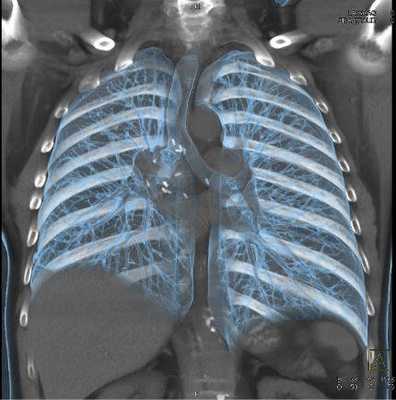

Мультиспиральная КТ грудной клетки, 3D-реконструкция

Специалисты выделяют в средостении три области: центральное (сосудистое пространство с перикардом и его содержимым, сосудами и лимфатическими узлами), переднее (жировая клетчатка, вилочковая железа, внутренние грудные артерии и лимфоидные ткани) и заднее (трахея, пищевод, нисходящая часть грудной аорты, лимфоузлы и паравертебральные пространства грудной клетки). Соответственно, все патологические процессы, которые протекают в данных зонах, могут быть видны.

КТ грудной клетки спиральная — позволяет получить изображения ребер, грудины, позвонков и регистрировать нарушение их взаимоотношений при аномалиях развития и травмах в условиях трехмерного моделирования (3D реконструкция). Особо показана при травмах груди, сочетанных травмах груди и живота.